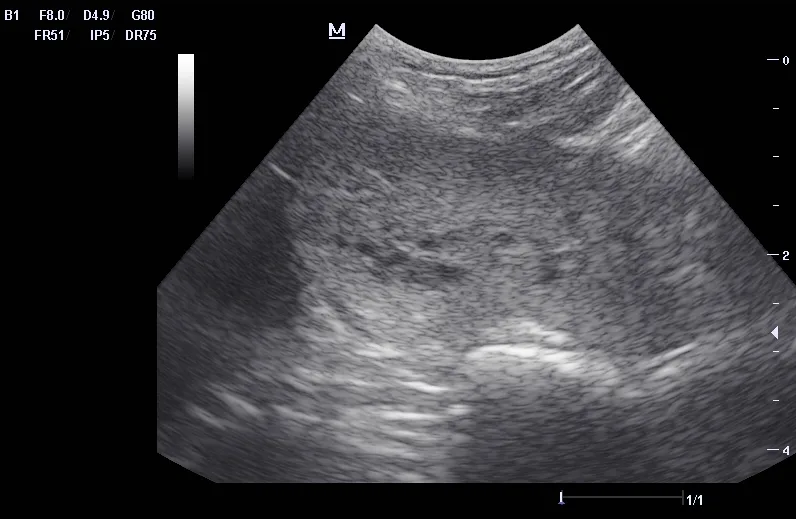

Ultrasound can be useful in evaluating the size, contour, and internal architecture of the prostate. A normal prostate appears homogeneous (Figure 1). The prostate becomes heteroechoic as a result of inflammation, hyperplasia, and neoplasia (Figure 2). The prostatic parenchyma can be focally or diffusely hypoechoic in cases of acute prostatitis or prostatic abscessation (Figure 3), as well as hyperechoic in cases of chronic prostatitis (Figure 4).

Ultrasound image of a canine prostate exhibiting chronic changes.

FIGURE 4

Prostate with chronic prostatitis. Several hyperechoic areas of mineralization can be seen.